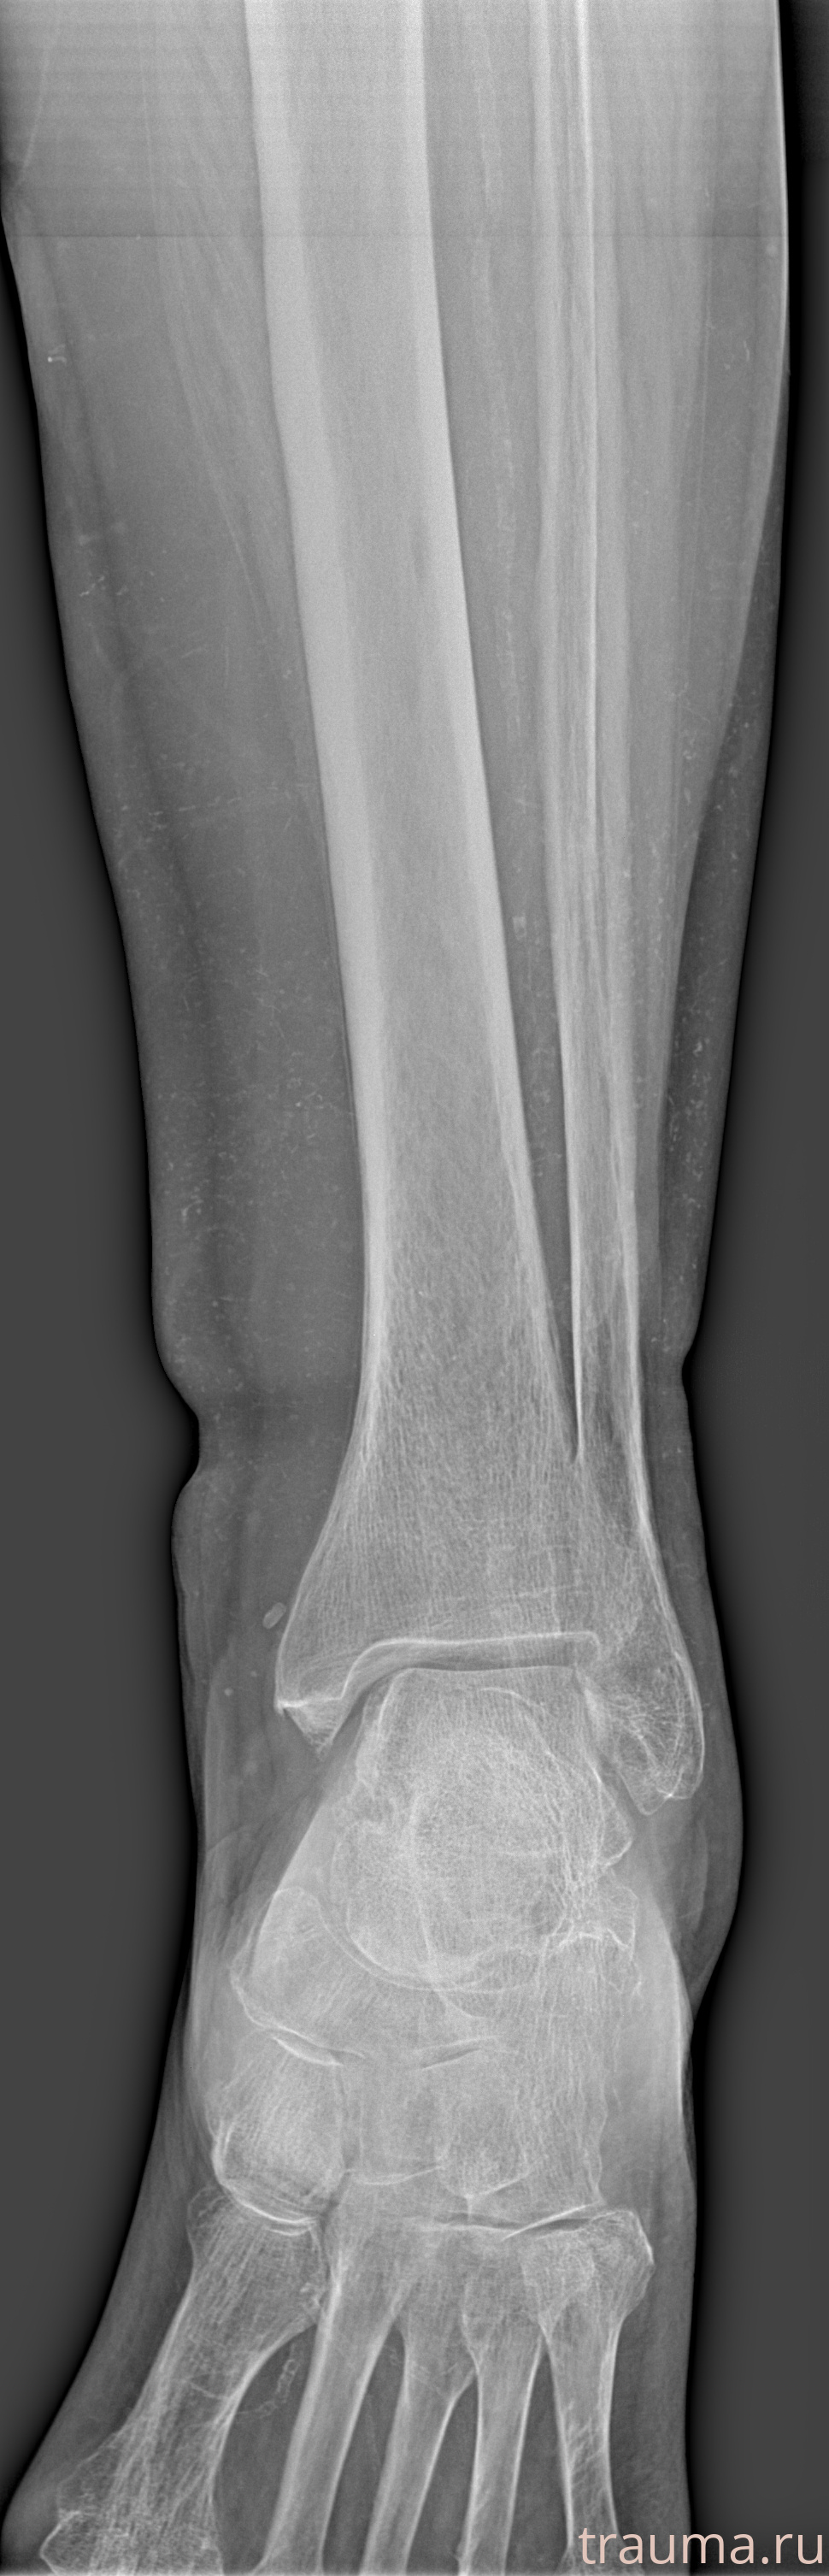

Рентгенограммы

Рентген на дому: по вашему адресу приезжает врач-рентгенолог, травматолог-ортопед с мобильным рентгеновским аппаратом, проводит диагностику травмы или заболевания, делает необходимые рентгенограммы, дает рекомендации по дальнейшему лечению. Получить качественные снимки в домашних условиях возможно благодаря уникальной методике, разработанной МосРентген Центром для института  Склифосовского